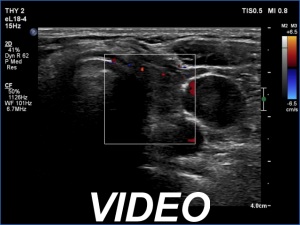

Ultrasonography. Both lobes had discrete lesions. The volume of the lobes were approximately one-tenth and one-third of a normal lobe, right and left lobe, respectively. The possibility of a true nodule should be considered in the event of the lesions in the left lobe.